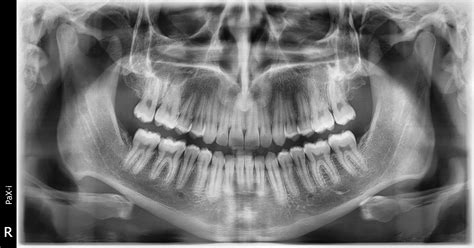

Muchas veces, estos dientes se descubren de forma accidental durante revisiones dentales rutinarias en niños o al realizar radiografías panorámicas para valorar la erupción dental.

Cuando se identifica un diente supernumerario en un niño, puede no dársele importancia ya que es confundible con un diente permanente que está asomando después de la caída del diente de leche. La realidad no puede estar más lejos de este pensamiento. La importancia de acudir a revisiones dentales de forma periódica durante la formación dental permanente de los niños aumenta cuando identificamos este tipo de anomalía. Los dientes de más pueden producir muchos problemas en el desarrollo de la dentadura. Identificar un diente supernumerario puede ser muy complicado. La mayoría de estos dientes no llegan a asomar en la encía o el paladar, por lo que se recomienda realizar un radiografía de vez en cuando para identificar este problema de forma prematura.

- Radiografía panorámica (ortopantomografía), para detectar dientes no erupcionados.

La ubicación precisa de los caninos afectados y la determinación de su relación con los incisivos adyacentes y las estructuras anatómicas es la parte del proceso de diagnóstico y es esencial para la valoración con éxito del tratamiento. Radiografías periapicales oclusales pueden ser útiles, pero la ortopantomagrafía y sobre un TAC dental son las pruebas de elección para el diagnóstico y valoración de tratamiento.